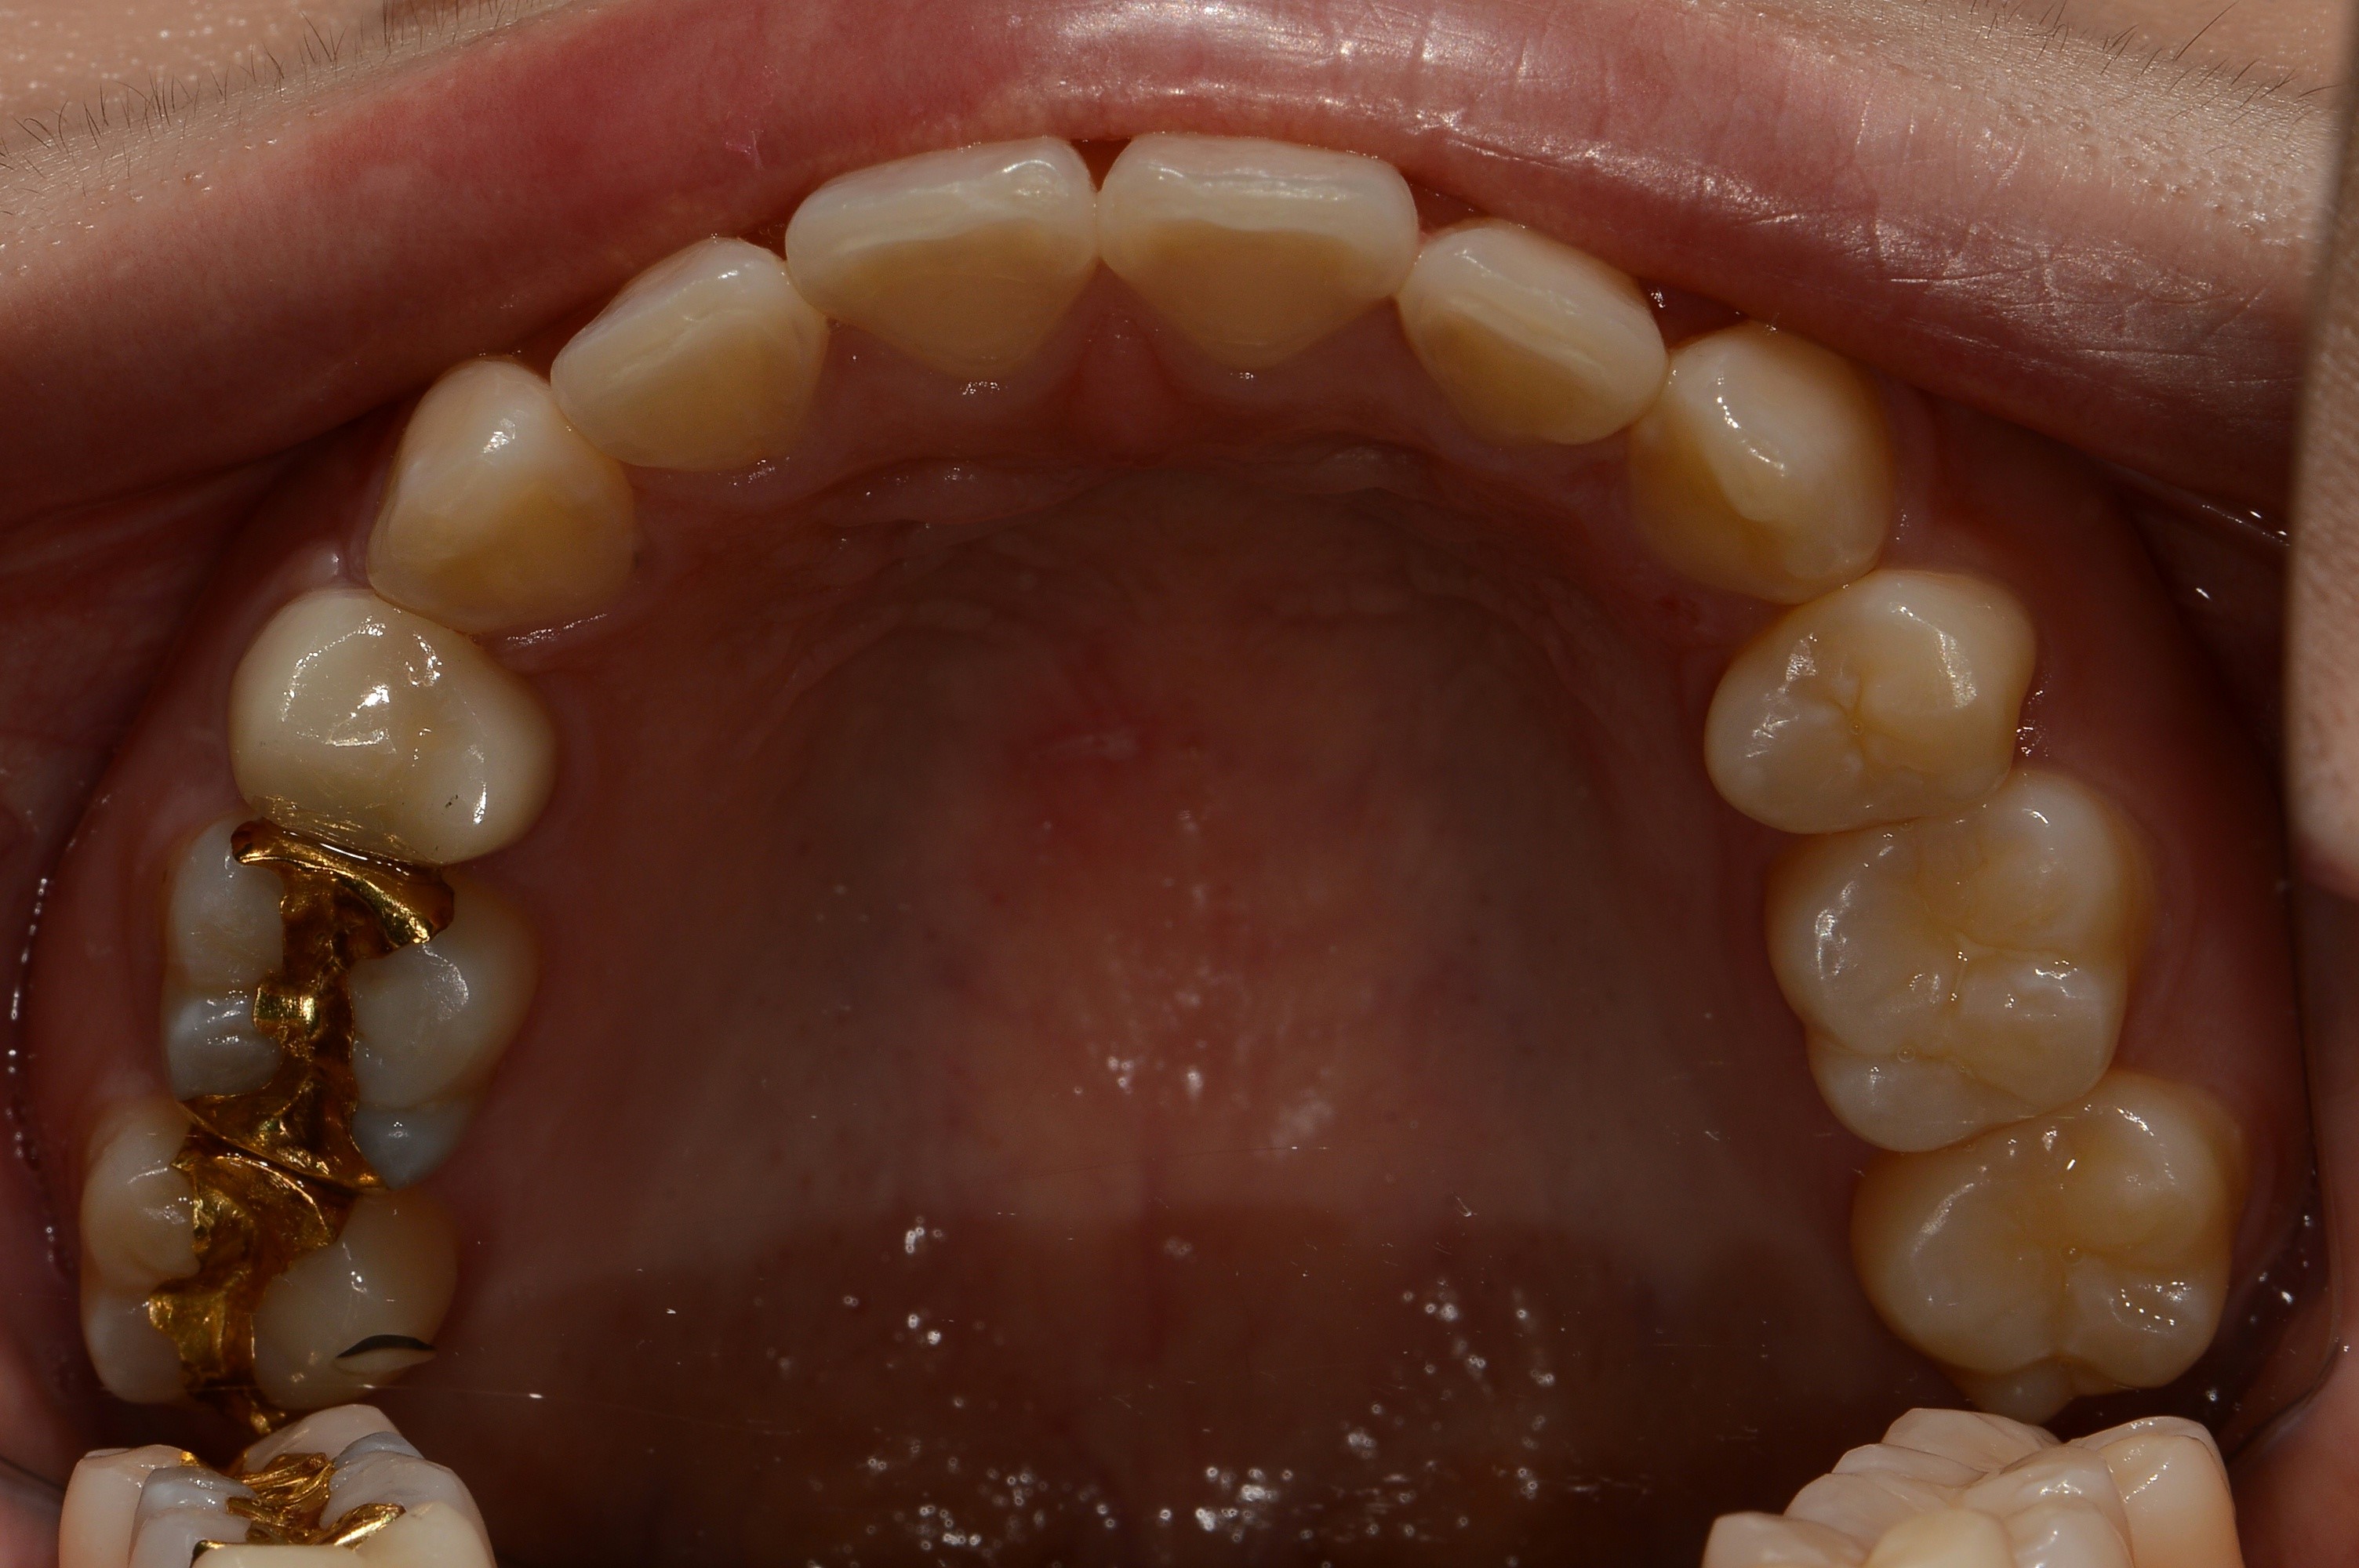

치료 전 사진입니다.